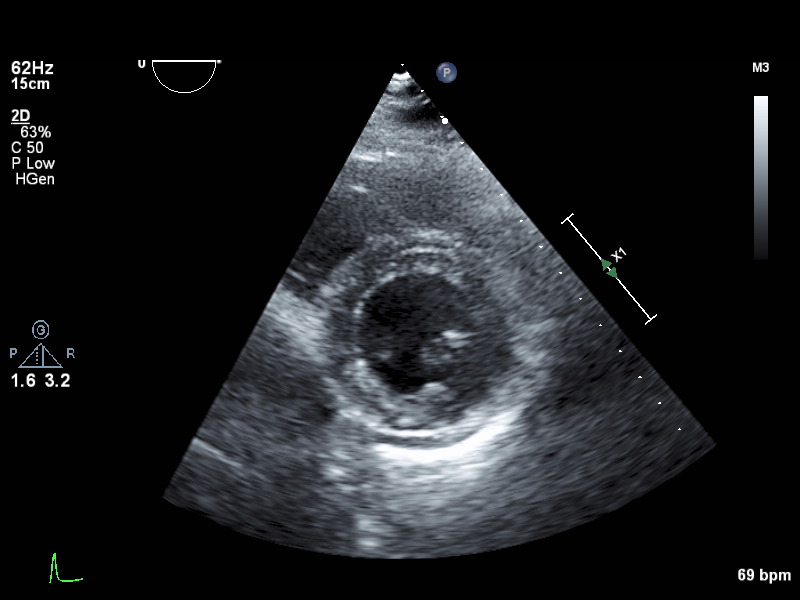

psax-lv-mid psax-lv-mid Left ventricle mid level

psax-lv-apex psax-lv-apex Left ventricle apex level